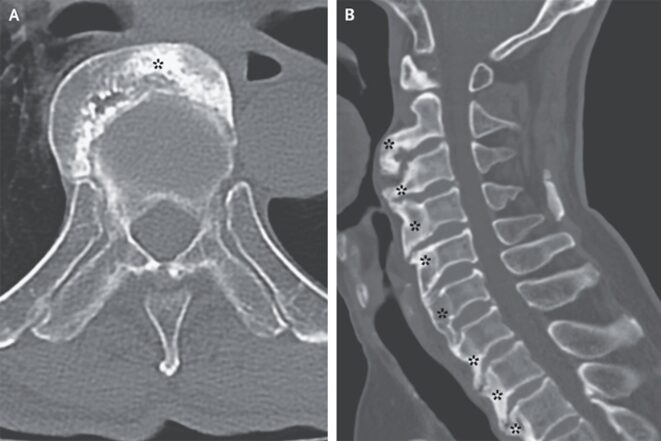

下咽頭の圧迫所見の精査が施行され、脊椎CTでは、椎体の前外側表面の広範な過骨症が示された(*)

「特発性骨格過骨症(脊椎靭帯骨化症の非炎症性疾患)」による中咽頭嚥下障害と診断された。